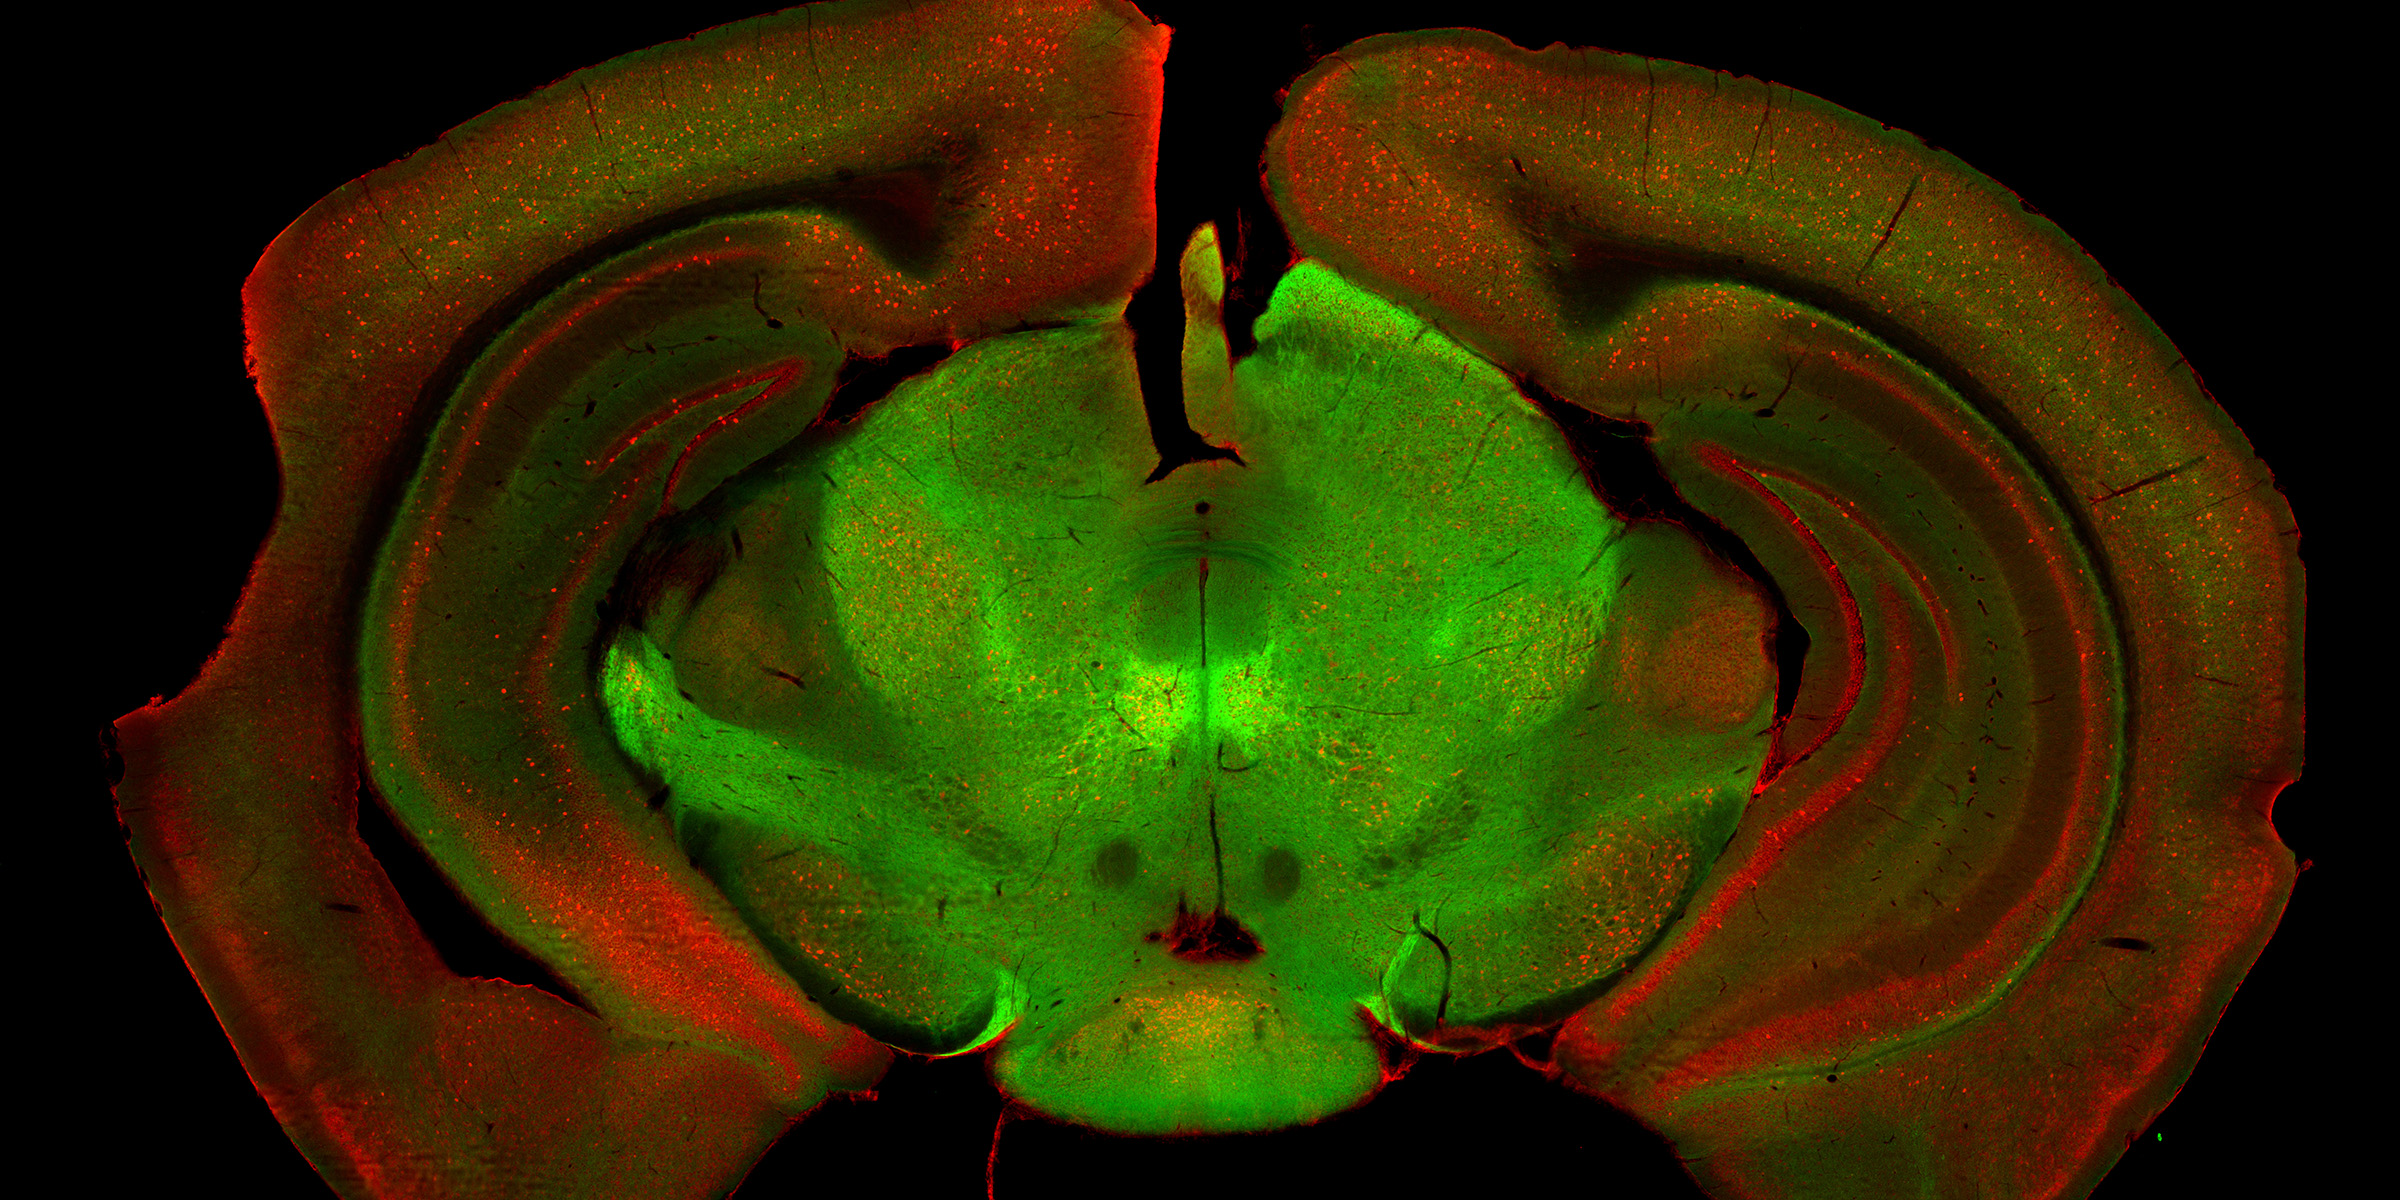

Whether we move our arms, legs or the entire body, every movement is centrally controlled by our brain. Different brain regions and neuronal networks play an essential role in this process. This includes the substantia nigra, which has been minimally investigated so far. Like a relay station, this region receives and distributes signals in order to appropriately orchestrate the execution of a desired movement. Using a mouse model, Prof. Kelly Tan's research group at the Biozentrum, University of Basel, has now identified two cell populations in the substantia nigra that are responsible for different aspects of locomotion.

The research team investigated the substantia nigra anatomically, genetically and functionally. It became apparent that this region consists of several different types of nerve cells. The researchers could identify two of the populations and describe them in more detail. While one population is responsible for initiating a motor task, the second population ensures the continuity of the desired movement. “The heterogeneity of neuronal populations in the brain, also in the substantia nigra, is a well acknowledged concept. In our study, not only we decipher the function of two nerve cell groups, but we also show that they work together to produce correct locomotion,” says Giorgio Rizzi, first author of the study.